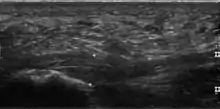

Thickened plantar fascia in ultrasound

The plantar fascia has three fascicles-the central fascicle being the thickest at 4 mm, the lateral fascicle at 2 mm, and the medial less than a millimeter thick.[20] In theory, plantar fasciitis becomes more likely as the plantar fascia's thickness at the calcaneal insertion increases. A thickness of more than 4.5 mm ultrasound and 4 mm on MRI are useful for diagnosis.[21] Other imaging findings, such as thickening of the plantar aponeurosis, are nonspecific and have limited usefulness in diagnosing plantar fasciitis.[13]